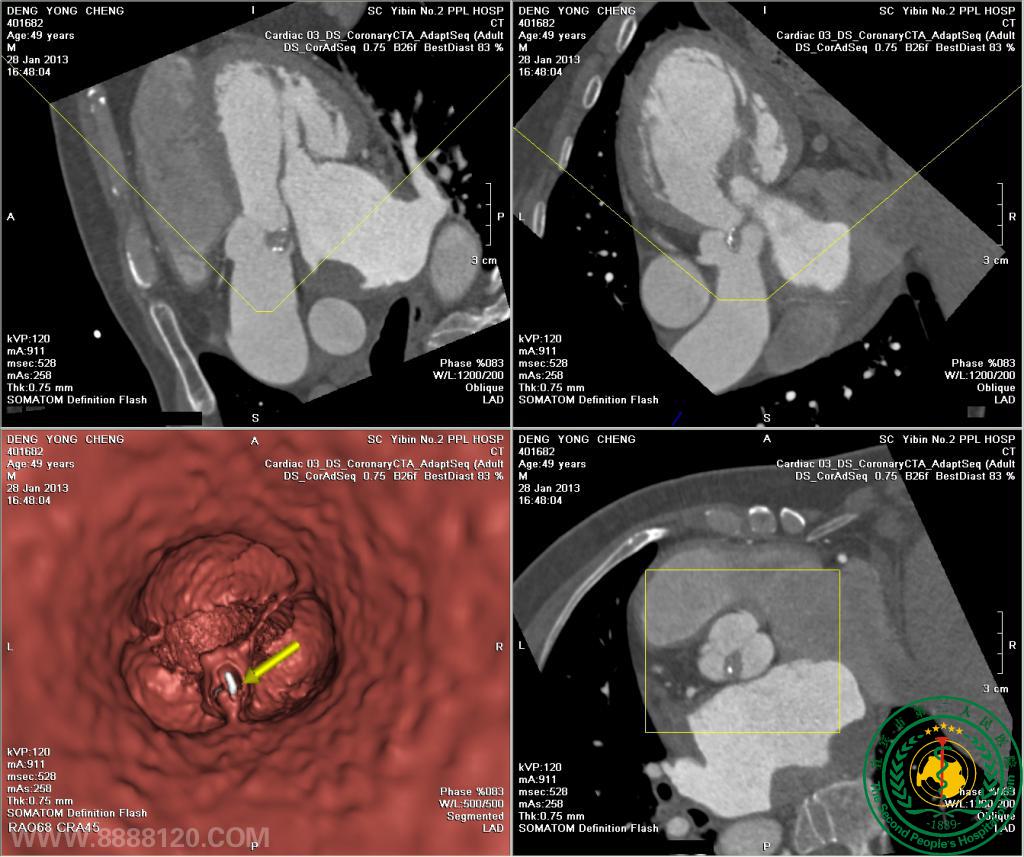

我院开展炫速双源CT对风心病的换瓣或成形术术前、术后评估技术

我院开展炫速双源CT对风心病的换瓣或成形术术前、术后评估技术3829